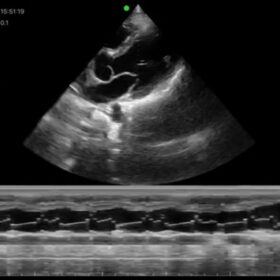

Cardio 2D, Color and PW doppler